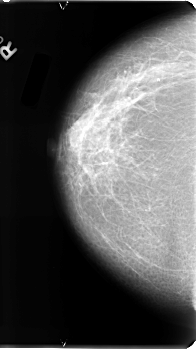

B_3100_1.LEFT_MLO

LEFT_CC LINES 4792 PIXELS_PER_LINE 2696 BITS_PER_PIXEL 12 RESOLUTION 50 OVERLAY

FILE: B_3100_1.LEFT_CC.OVERLAY

TOTAL_ABNORMALITIES 1

ABNORMALITY 1

LESION_TYPE MASS SHAPE ROUND MARGINS MICROLOBULATED

ASSESSMENT 4

SUBTLETY 3

PATHOLOGY BENIGN

TOTAL_OUTLINES 1

BOUNDARY